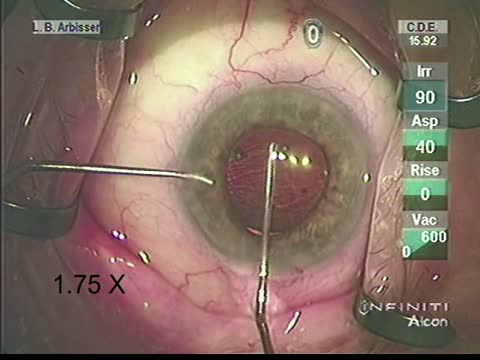

Morgagnian Cataract

Lisa Brothers Arbisser, MD